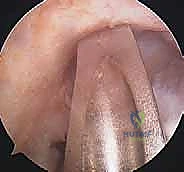

الخطوة الأولى: الفحص بالمنظار الجراحي 4K

يستخدم الدكتور